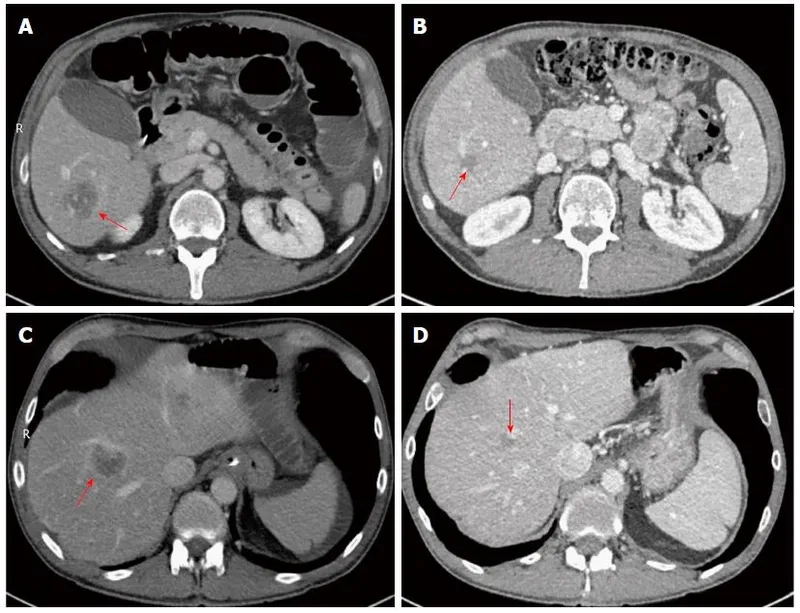

• This abnormal protein can also get stuck in the liver, leading to the buildup that causes significant liver disease in some individuals.

• In others, AAT deficiency manifests as liver disease, with symptoms like jaundice (yellowed skin), fatigue, and swelling in the legs and belly.

Image of the disease Alpha-1 Antitrypsin Deficiency